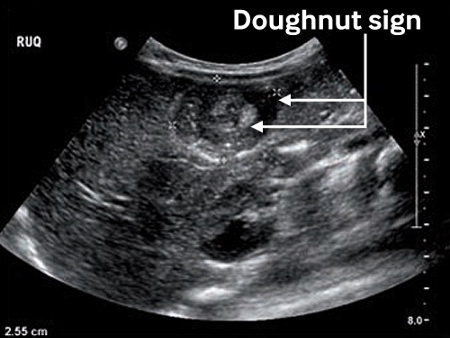

Abdominal ultrasound - shows a target like mass. Colour Doppler can show if bowel is ischaemic.

Results: Target sign (variants include bull’s eye sign, doughnut sign, crescent-in-doughnut sign, and multiple concentric ring sign); pseudokidney sign; sandwich sign; abnormal Doppler flow